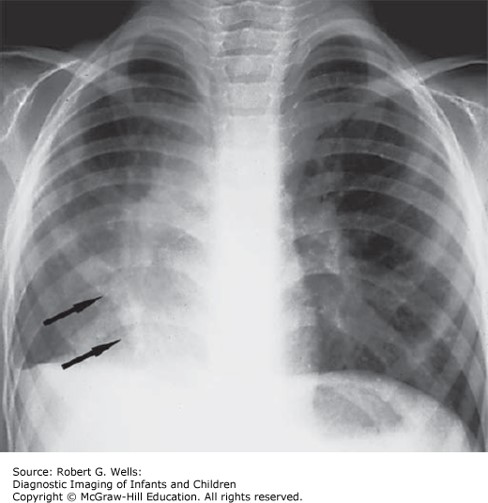

Hypogenetic lung syndrome. The right lung is small and there is rightward mediastinal shift. The pulmonary vessels in the right lung are small and there is secondary enlargement of vessels in the left lung. There is a curved vascular structure (arrows) at the right lung base, representing an anomalous pulmonary vein; this is the scimitar sign.

Source: Wells RG. Diagnostic Imaging of Infants and Children; 2015.